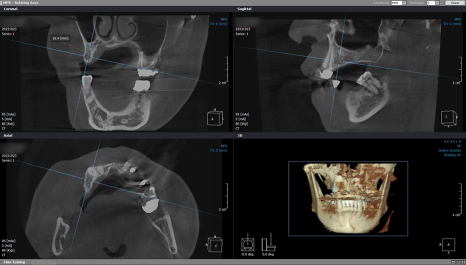

이어서 우측 임플란트를 위해

재검사를 시행했습니다.

처음과 같이 큰 변화는 없었지만

오차 없이 인공 치근을 식립하려면 검사는 필수죠 ^^

4개월의 골 유착 기간을 갖고

내원해 주신 환자분의

#14번 치아는 본을 뜨고 보철물 수복을 해드렸으며

2차 수술을 진행한 #16, #17, #46, #47번은

잇몸을 열고 커버 스크류 제거 후

힐링 어버트먼트를 체결해 드렸답니다.

도착한 맞춤 브릿지를 씌워드리고 나서

마무리로 치근단 사진 촬영을 해서

주위염은 없는지 체크했습니다.

전체 브릿지 임플란트 완성 후 교합 측정 시

상하악이 알맞게 다물렸으며

내구성 좋은 지르코니아 보철물을 수복했기 때문에

자연치와 조화롭게 어울림은 물론

단단한 식품도 저작할 수 있는 강도를

회복하시게 되었습니다.